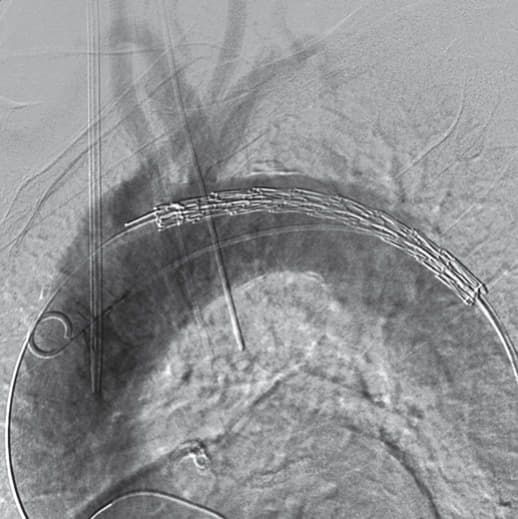

右総大腿動脈に6 Frシースを留置し、アクセスとした 。ラジフォーカスTMガイドワイヤーM**および 5 Frピッグテールカテーテルを上行大動脈まで進行させ、manipulateしたEgoist® EGU35-AC300Q (Arch Curve)ガイドワイヤーを大動脈基部まで到達させた。この時点で透視下にガイドワイヤー押し付けを行い、安定した状態で大弯側に押し付け可能なこと、左室内へ迷入しないことを確認した。22 Frゴア®ドライシール フレックス イントロデューサシースを進行させ、引き続きTAG® コンフォーマブル ステントグラフトTGMR373710Jを適正位置まで進行させた。DSAを施行し、左総頚動脈(LCCA)および左鎖骨下動脈(LSCA)の位置を確認した。ここからは、術者(ドライシールシース固定およびデリバリーカテーテルの操作)・助手(デリバリーカテーテルの固定、ガイドワイヤーの押し付け)の共同操作にて一次・完全展開を行った。ガイドワイヤーを軽く押し付けた状態で、パーシャルアンカバーステントがLCCAに若干かかる位置で一次展開を施行した。ガイドワイヤーの押し付けを加えて、LCCA直下にパーシャルアンカバーステントが位置するように微調整を行った。DSA上のZone 2レベルの小弯側に合わせて、アンギュレーションコントロールダイヤルを回転させて至適な角度に調整した。ガイドワイヤーを押し付けた状態で完全展開を施行した。DSAを施行し、コアキシャルに留置されていること、特に小弯側が至適角度で留置されていることを確認し、この時点でのアンギュレーションコントロールは必要ないと判断した。ガイドワイヤーを用いて、慎重にピッグテールカテーテルを抜去し、引き続き完全展開を施行した。DSAを施行し、エンドリークが無いことを確認した。左上腕動脈よりアクセスし、LSCA根部で造影した。DSA上、明らかなType ll エンドリークを認めず、deployment sleeve部分を含むステントグラフトにてLSCA根部が完全に被覆・閉鎖されていることが確認できた。